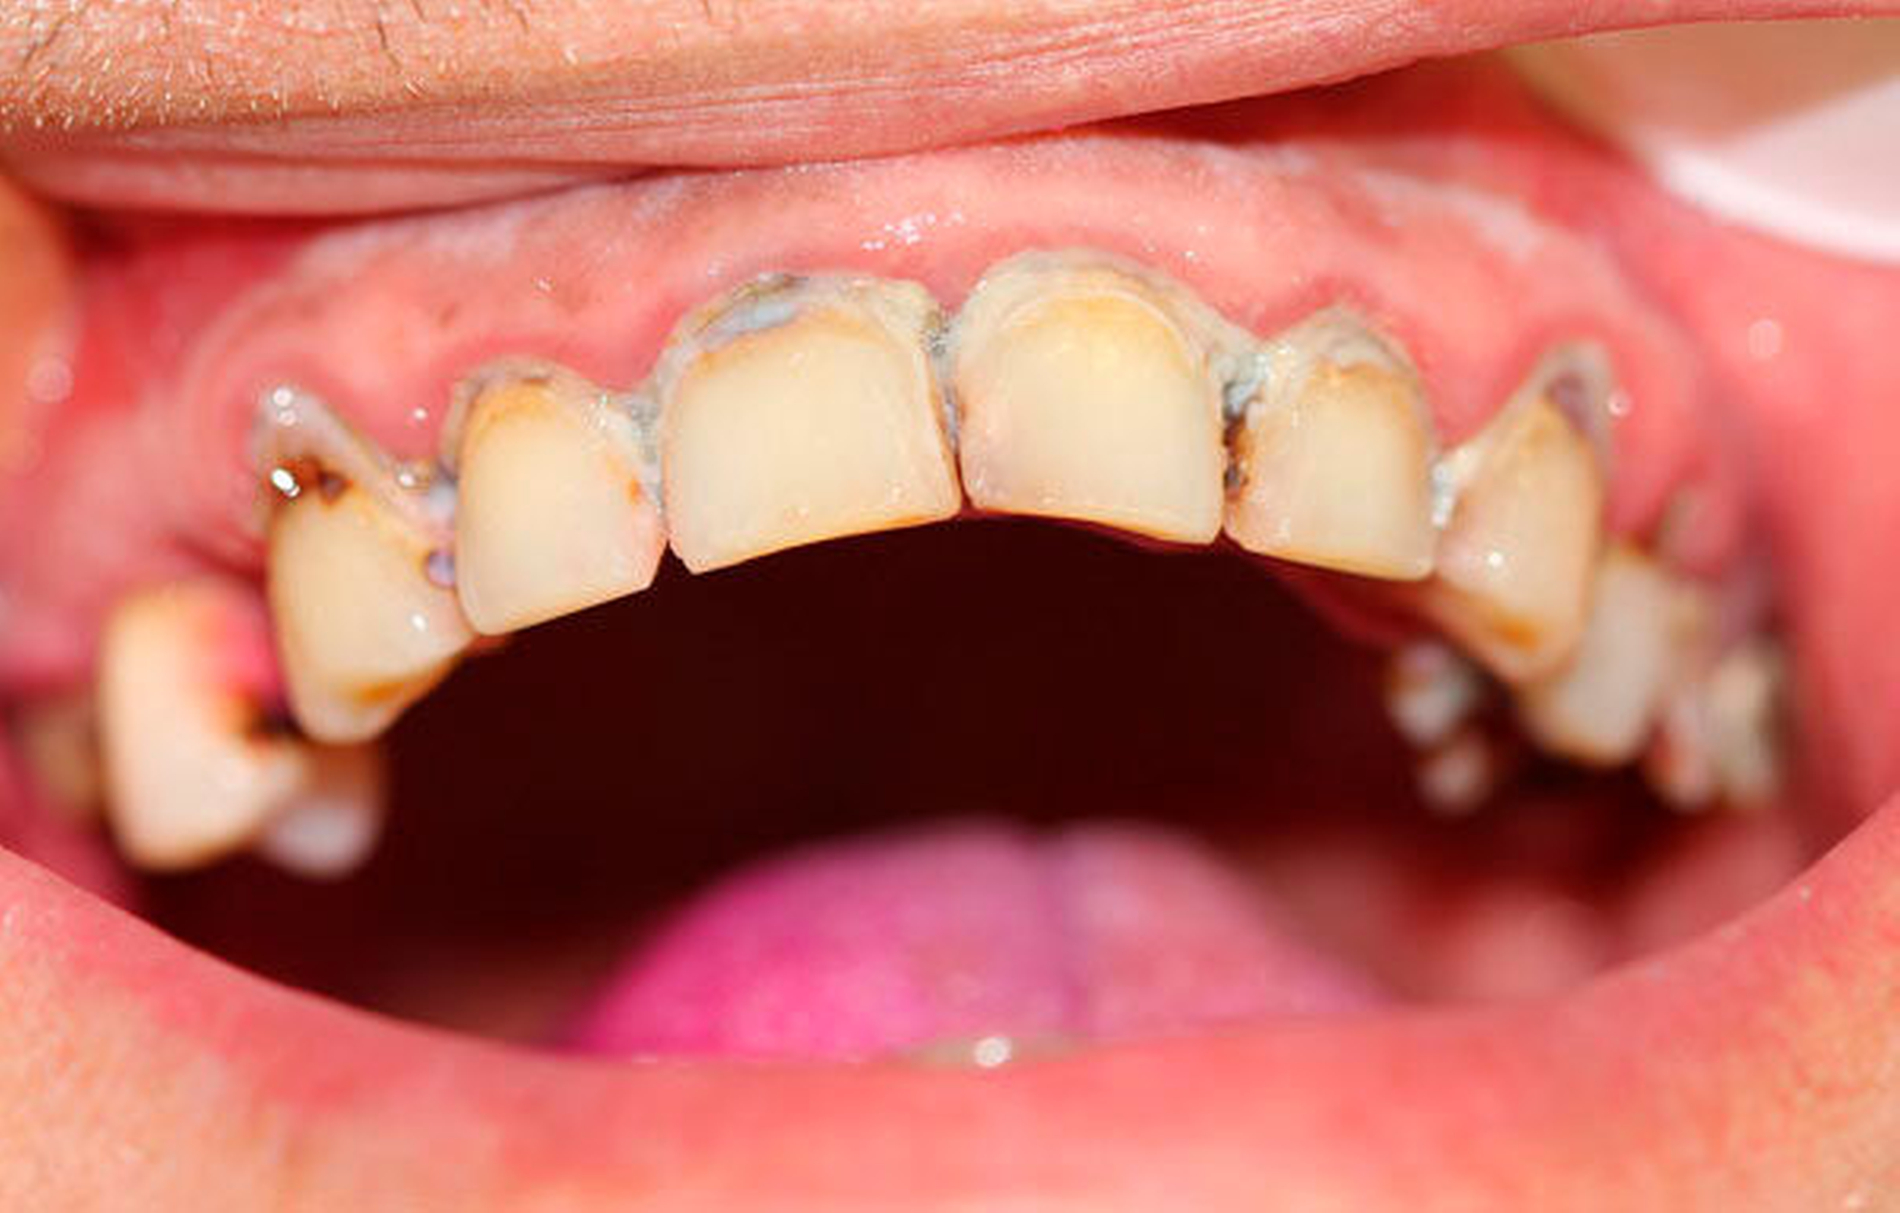

Bei chronischem Crystal-Meth(CM)-Konsum wurde eine Vielzahl körperlicher und psychischer Langzeitwirkungen, beispielsweise Herz-Kreislauf-Erkrankungen, strukturelle Hirnschädigungen und Persönlichkeitsveränderungen, beobachtet [Hamamoto et al., 2009]. In der aktuellen Literatur werden außerdem schwerwiegende Auswirkungen auf die Zahn-, Mund- und Kieferregion beschrieben [Hamamoto et al., 2009; Rhodus et al., 2008]. In den USA, wo nach Schätzungen knapp ein Drittel der weltweit über 30 Millionen CM-Abhängigen lebt, wurde 2005 erstmals der Begriff des „Meth mouth“ in der Fachliteratur genannt [Hamamoto et al., 2009; Rhodus et al., 2005] (Abbildung 1). Dabei wurden fünf Kardinalsymptome beschrieben: 1. Grassierende Karies (Abbildungen 2 und 3), 2. Gingivitis und Parodontitis, 3. Xerostomie, 4. Bruximus und 5. Trismus [Hamamoto et al., 2009; Rhodus et al., 2008].